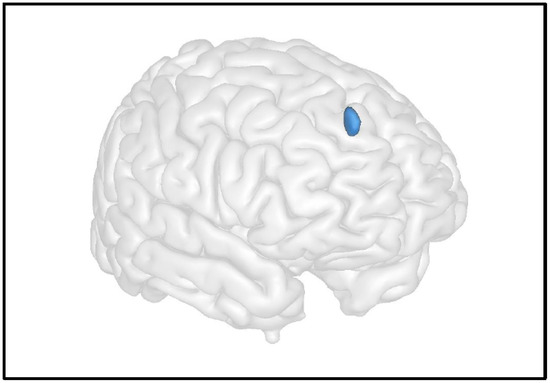

6.1. Grey Matter